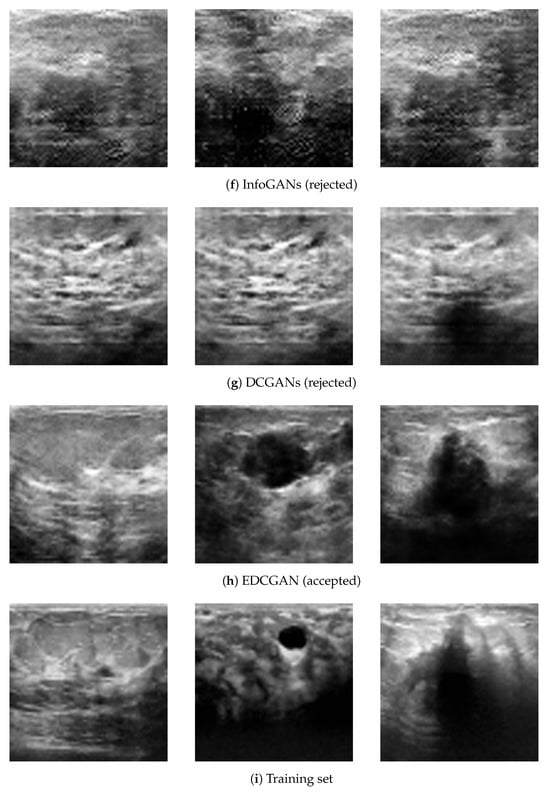

Augmentation of Small Ultrasound Databases: A Practical Approach

by Onsasipat Kasamrach, Thiansiri Luangwilai and Stanislav Makhanov

Mathematics 2026, 14(4), 646; https://doi.org/10.3390/math14040646 - 12 Feb 2026

Generative Adversarial Networks (GANs) have emerged as a promising tool for augmenting medical image datasets used by AI solutions. However, GANs trained on small datasets (300–500 images) frequently encounter mode collapse, overfitting, and instability, which hinder their practical application. Many GAN-generated images look unrealistic. The Enhanced Deep Convolutional GAN (EDCGAN) is introduced to generate high-quality synthetic images of breast US (BUS). The model includes an experimental design for the Discriminator and Generator. The main components are spectral normalization (SN), the Squeeze-and-Excitation (SE) block, and the Scaled Exponential Linear Unit (SELU). One of the basic versions of DCGAN is considered for the proposed modifications. The stopping criteria are based on the convergence of the smoothed loss function and the constraints imposed on the Discriminator. The contribution is a combination of the above modifications and postprocessing based on the visual evaluation by radiologists and selected image processing metrics. The Inception Score (IS), the Structural Similarity Index (SSIM), and the Mean Squared Error (MSE) comply with the results obtained in the preceding works. The efficiency of augmenting the US data has been verified on a DL classification based on ResNet-18. The tests against training on a non-augmented data outperform ResNet by 5% and by the data augmented by the previous DCGAN by 3%. These numbers are substantial since this variant of ResNet has been pre-trained on 1000 categories by ImageNet-1K, including 1.28 million images. Additionally, the model wins the “Guess-the-real-image” game, competing with seven preceding GANs. Full article